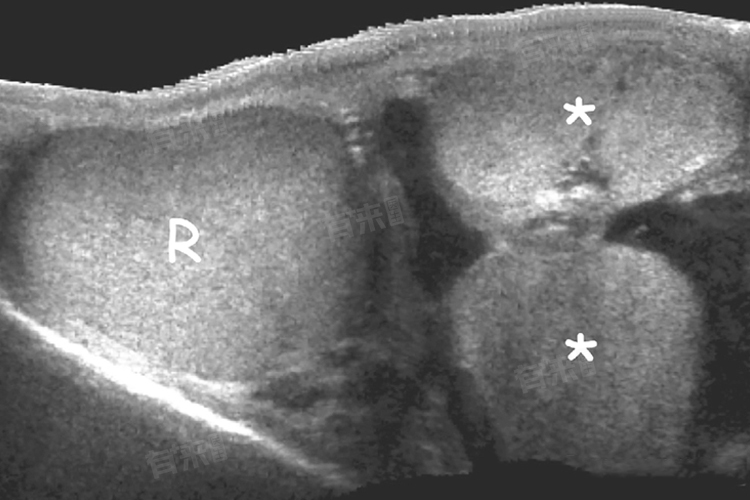

- 超声检查是重要手段之一,利用高频声波成像,清晰呈现睾丸内部结构,包括附睾、精索等,可精准探测是否存在囊肿、肿瘤、炎症等病变,明确三个睾丸各自的健康状况,其无痛、无创且分辨率高,能为诊断提供关键图像信息。